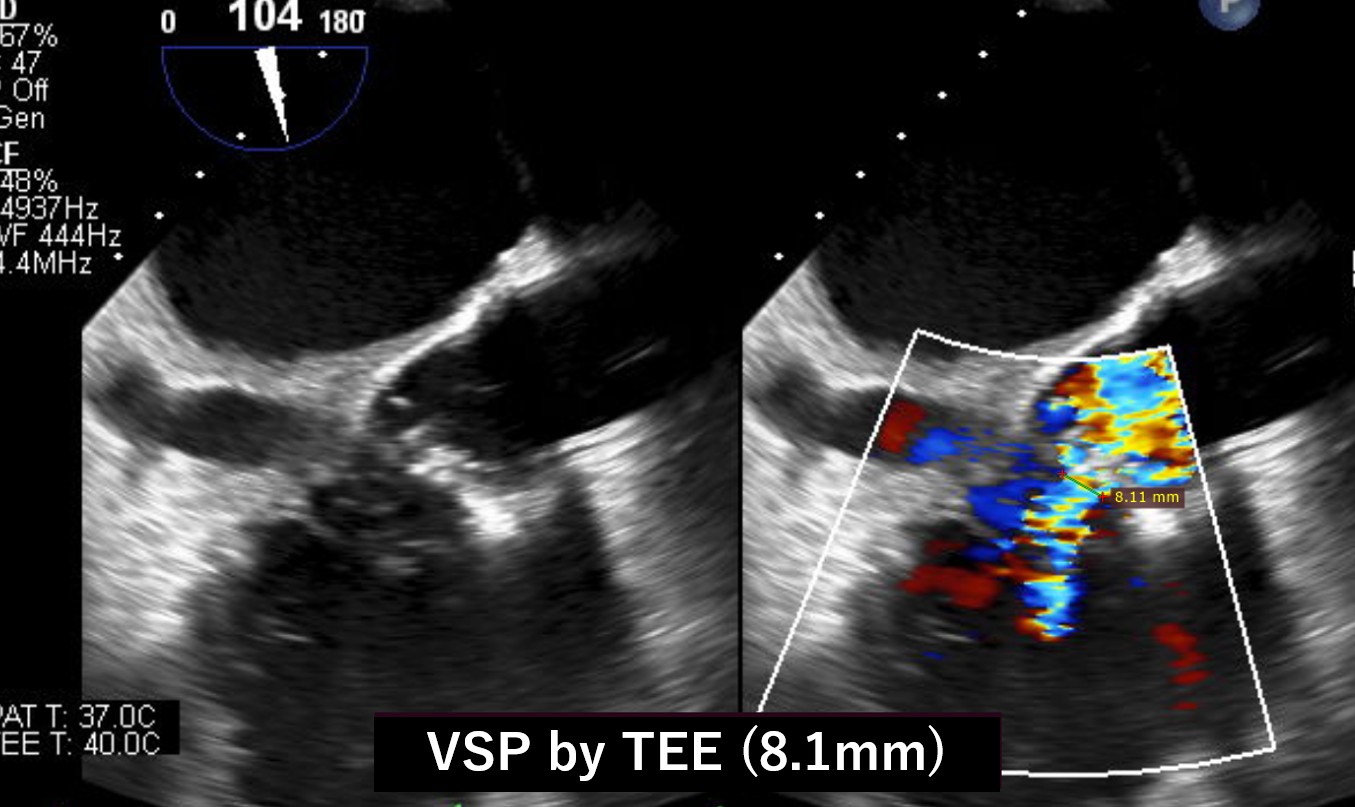

Our heart team decided to perform both VSP and PVL closure by transcatheter technique because of the previous multiple open-heart surgery with high surgical risk score. Before percutaneous VSP closure, the oximetry-run exams revealed Qp/Qs 1.3 but the transesophageal echo(TEE) showed the EROA of aortic PVL was 0.51 mm2 and the defect size was 10.5 x 5.4 mm which meant severe PVL. We also confirmed the defect size of VSP with TEE, and the size was 8.1mm.

We performed this procedure under generalanesthesia with TEE. The first step was to close the VSP so that we manipulateda 5 Fr. Destination sheath with diagnostic JR4 catheter as mother and childtechnique. Inside of the system, 0,014-inch wire and microcatheter was advancedleft ventricle(LV) from aortic PVL. We turned the wire inside LV to access theVSP. We succeeded to have the wire advance to right ventricle(RV) through the LVand PVL. The next step was creating AV loop so that the 0.014 wire was snaredin the pulmonary artery and pulled out from right femoral vein. After creatingAV loop with 0.014 wire, the loop was exchanged to 0.035 wire and AMPLATZERDuct Occluder 6/4 was implanted into VSP. After closing VSP, we accessed insidethe PVL again and the wire was switched to super stiff one to advance theDestination sheath inside LV. Once the sheath was advanced in LV, 8mm AMPLATZERvascular plug 2 was deployed to close the PVL.